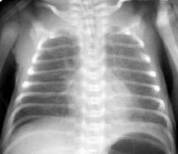

Резкое снижение пневматизации легких, воздушные бронхограммы, границы сердца не различимы, "белые лёгкие" (Рис.7).

Рисунок 7. РДС. Рентгенограмма грудной клетки в прямой проекции, в горизонтальном положении. Интенсивное мелкоточечное затемнение легочных полей - симптом "матового стекла", на фоне которого не дифференцируется тень средостения. Визуализируются линейные просветления, обусловленные заполненными воздухом бронхами - "воздушная бронхограмма". (Диагностика и лечение РДС недоношенных // метод. рекомендация, 2007)